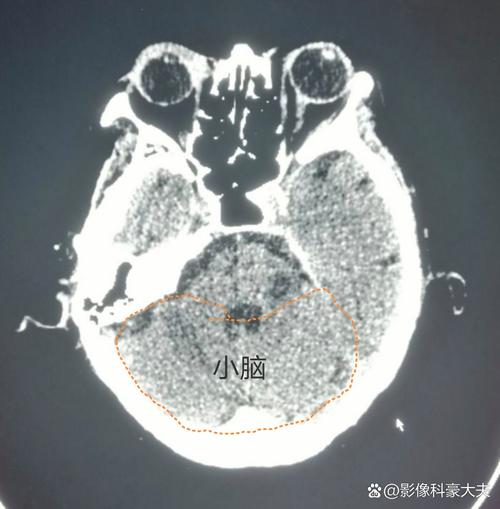

C. 亚急性期(发病后2天 - 3周)—— 显示最清晰

这是CT诊断脑梗的“最佳时期”,在这个阶段,缺血坏死的脑组织会发生明显的变化:

- 典型的低密度灶:在CT图像上,梗塞的区域会呈现一个非常清晰、边界相对明确的低密度(发黑)区域,这是因为坏死的脑组织水分增多,密度降低。

- 占位效应:如果梗塞面积较大,周围会出现明显的脑水肿,导致脑室受压变形,中线结构移位。